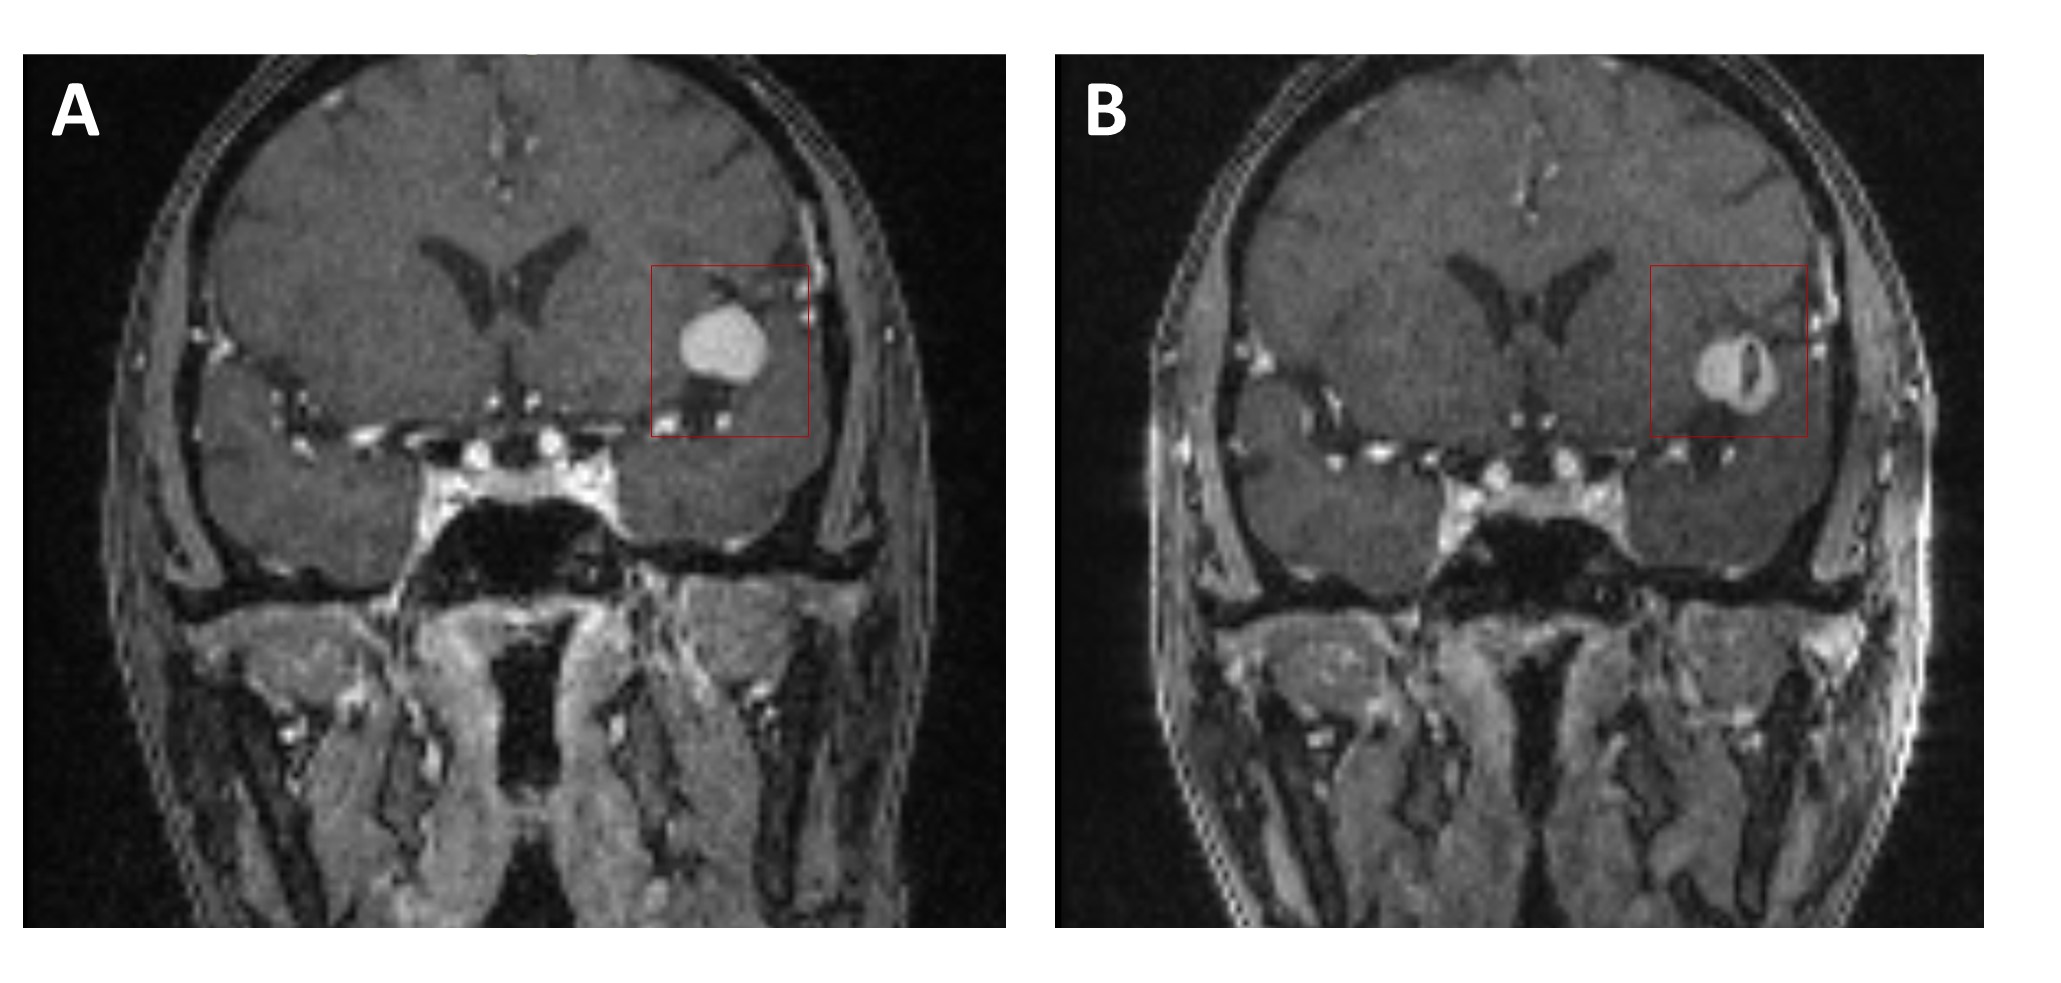

The 4D Flow MRI images were collected from nine patients with aneurysms receiving flow diverter stents implantation at Changhai Hospital (Shanghai, China). One patient with giant aneurysm on left internal carotid artery (ICA) and one patient with giant aneurysm on middle cerebral artery (MCA) were excluded because the blood flow patterns were too complex to analyze. In our study, seven patients (mean age, 55 ± 10.5 years; 1 male) were included (Table 1). Informed consent was obtained from all the patients. The dataset example was shown in Figure 1.

Figure 1. Dataset example before and after surgery. (A) 4D Flow MRI image before flow diverter stent implantation. (B) 4D Flow MRI image after flow diverter stent implantation.